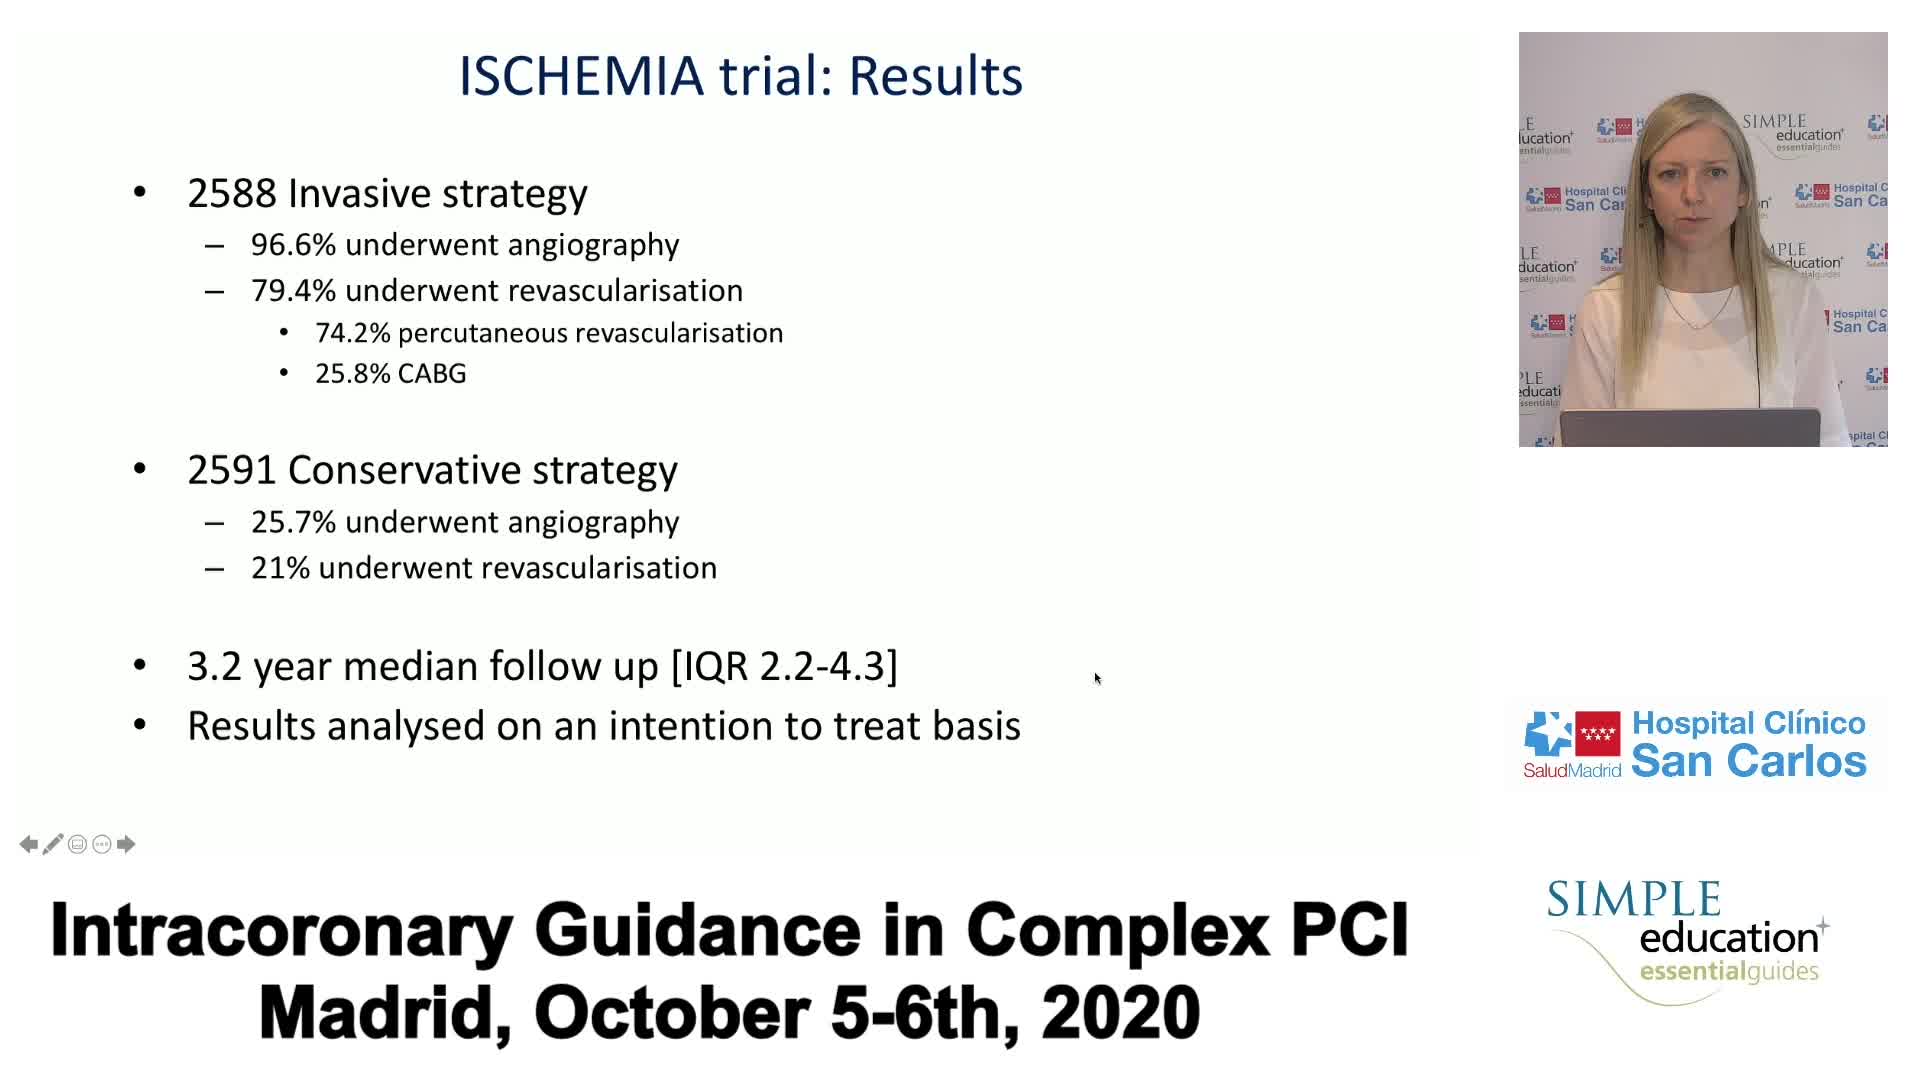

Revascularisation in stable angina: a contemporary perspective - Dr Rasha Al-Lamee